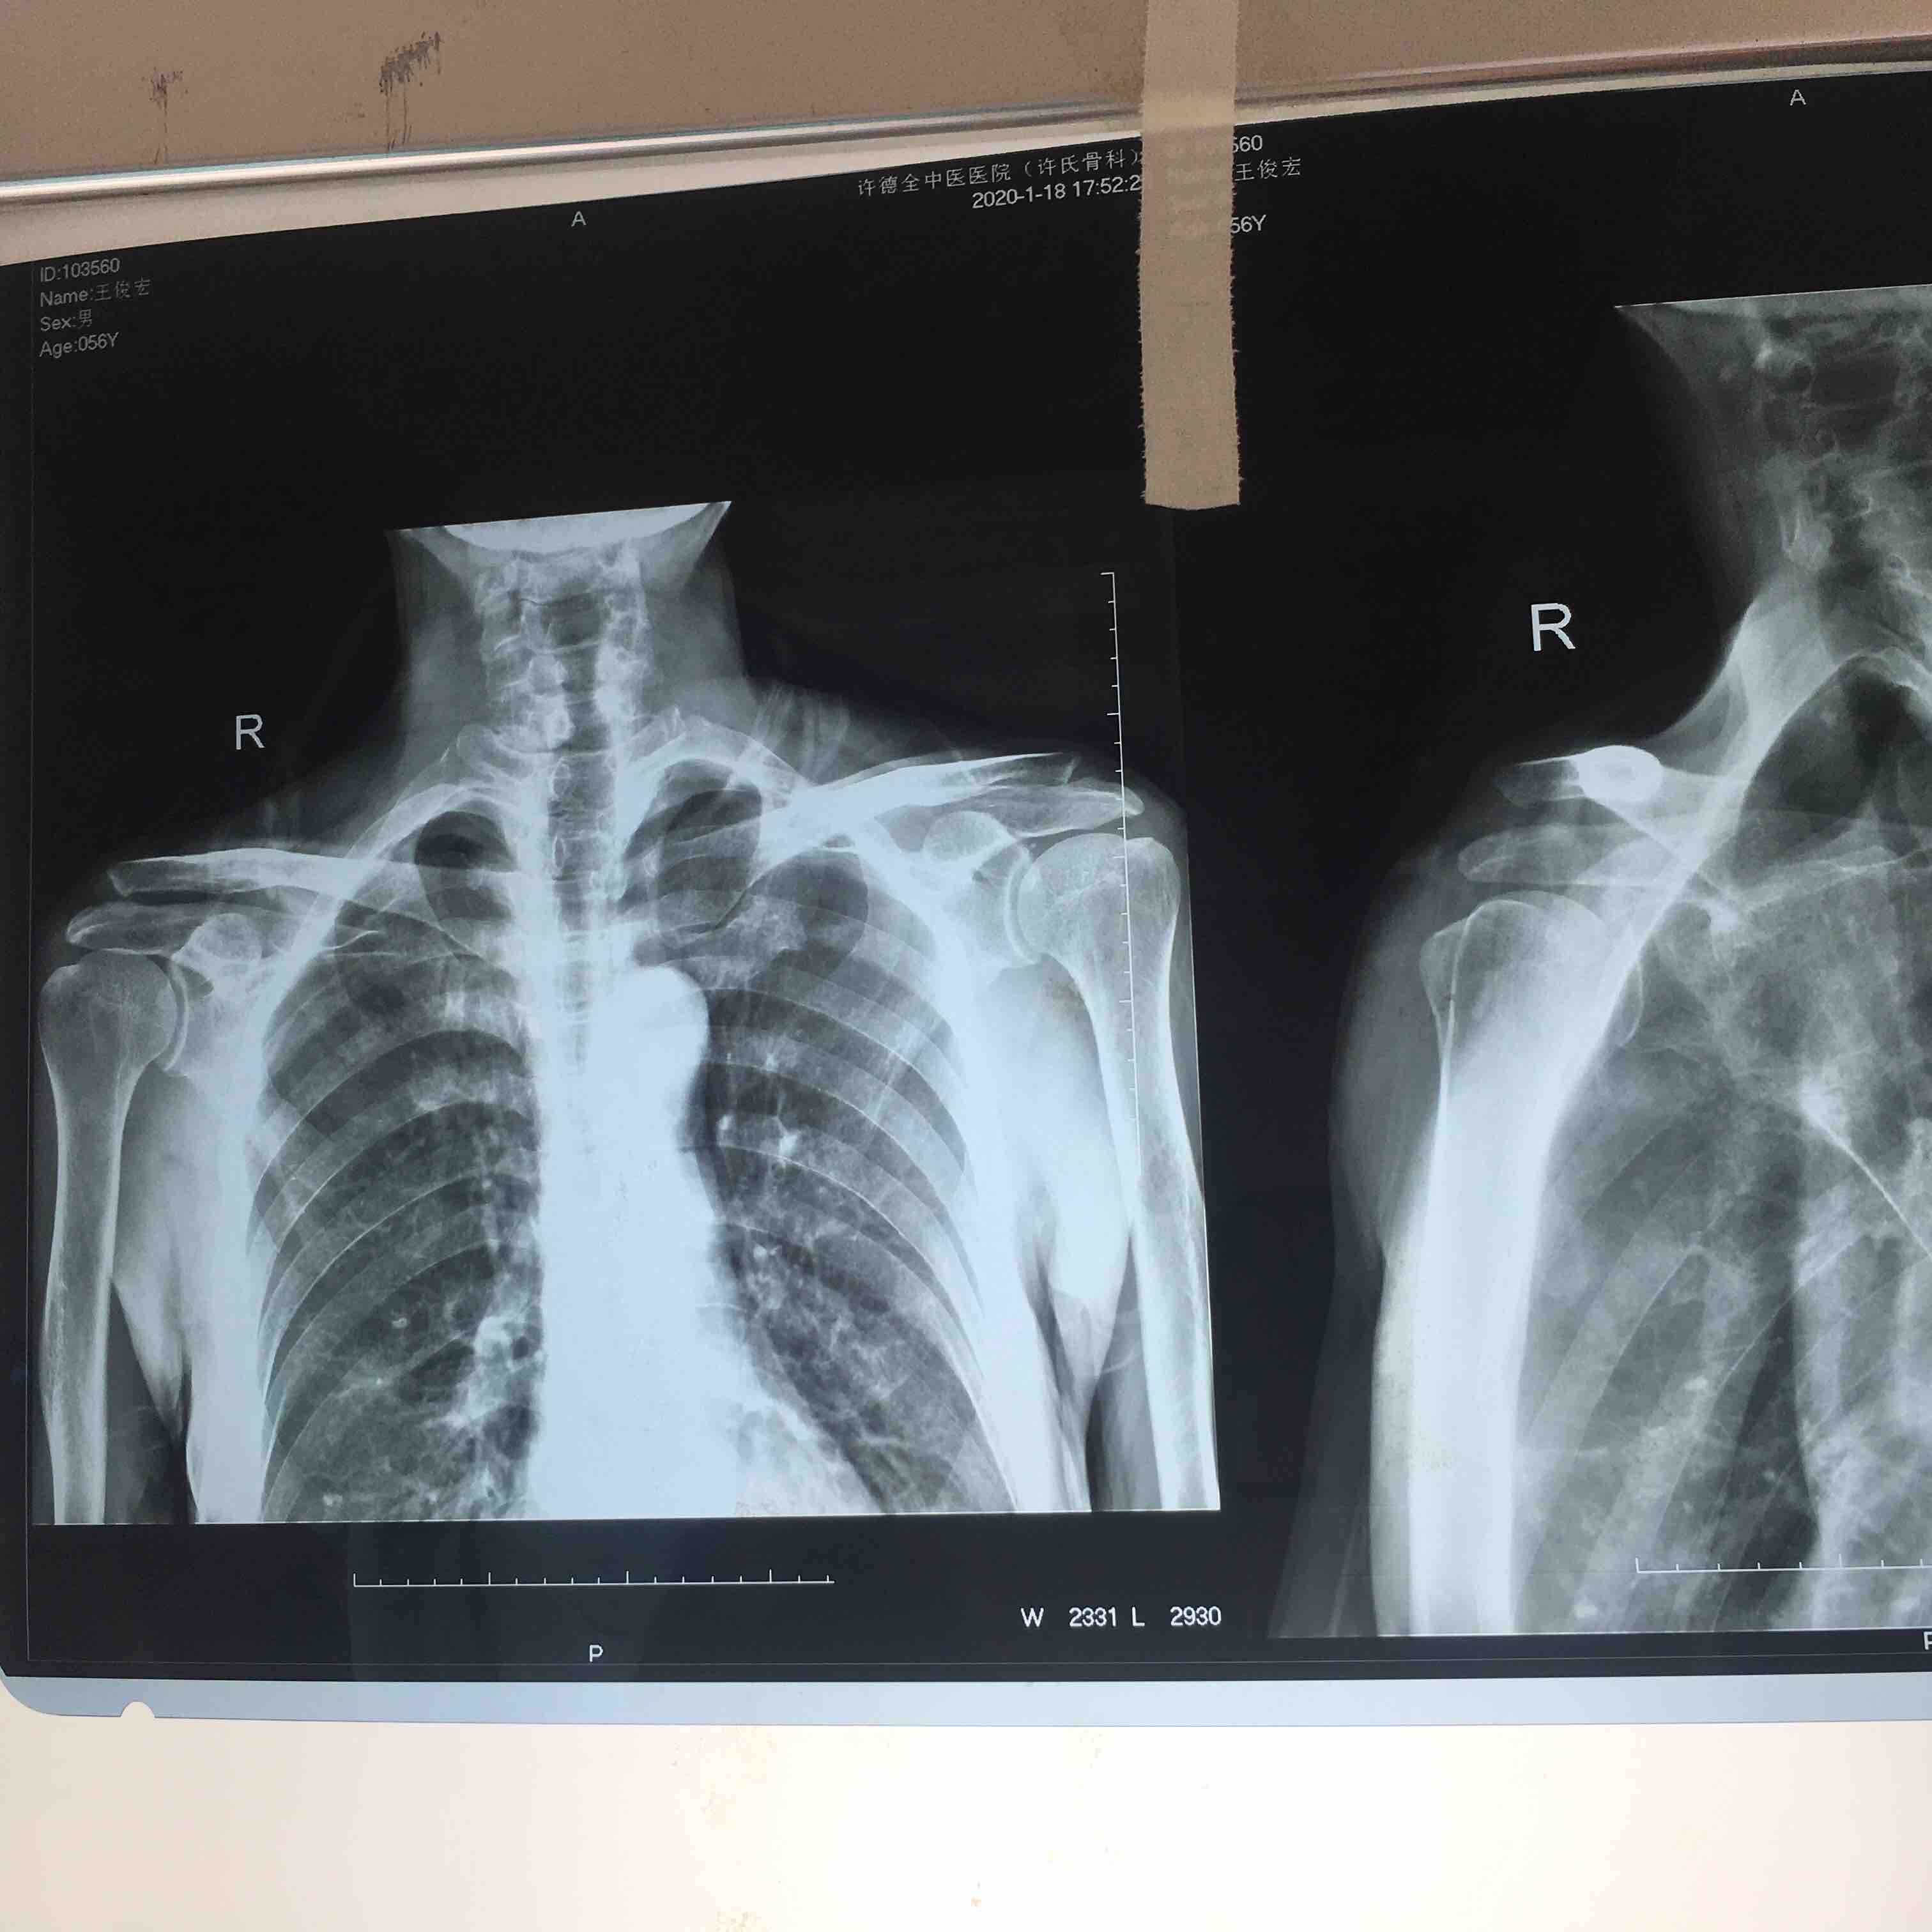

关节脱位 肩锁关节脱位

摔伤后右肩部肿痛,活动受限1天入院。既往身体健康,无特殊不良嗜好。

生命体征平稳,心肺复未见异常。右肩部肿胀,局部皮色皮温正常,压痛明显,琴键征阳性,肩关节活动受限,末梢血运感觉正常。

右肩锁关节脱位在臂丛麻醉下行切复内固定术,术后抗炎,消肿等处理。